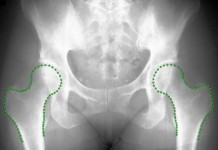

Программное обеспечение повысит качество диагностики артрита суставов

Несмотря на богатство технологических решений, которыми сейчас могут похвастаться буквально каждая из отраслей человеческой деятельности сегодня, не всё пока что идеаль...